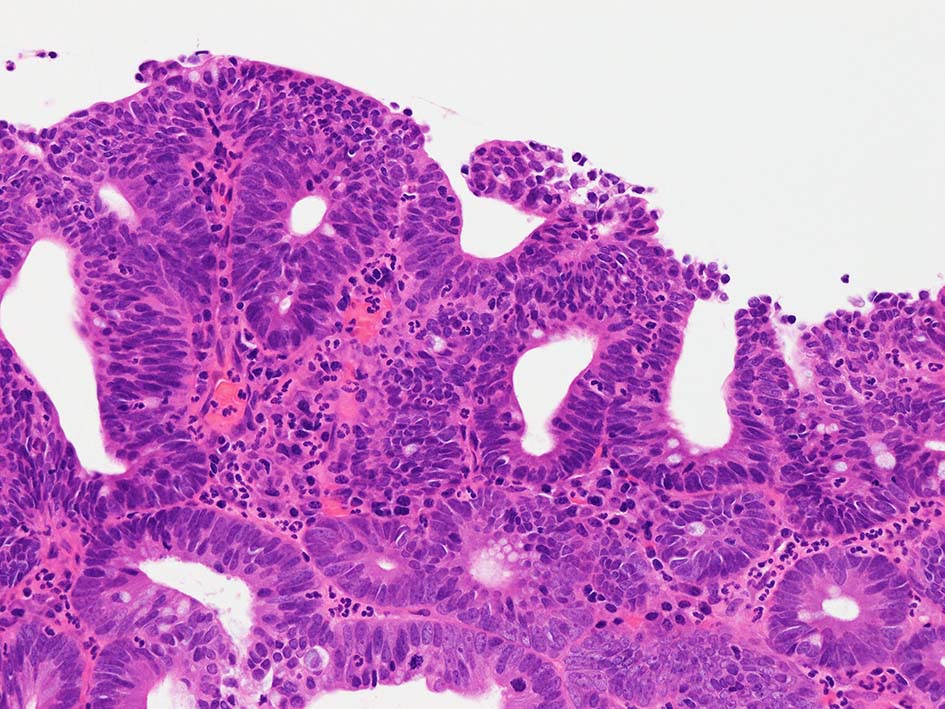

腸管型の腺癌。大腸の高分化腺癌と組織学的に区別は難しい.

neutrophilic exudate の付着する腸管型腺癌部分. 核はより腫大し円形、vesicularとなっている. 上記腸管型とはCK20, CK7のそまりが異なっていた. 変性のためかもしれない.